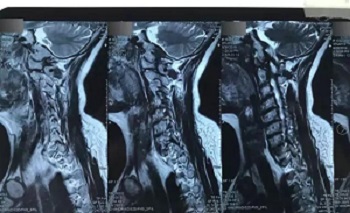

八、拍片子时,如果一张片子上有两张图像的时候,合起来拍一张,分开再各拍一张(如以下三张)